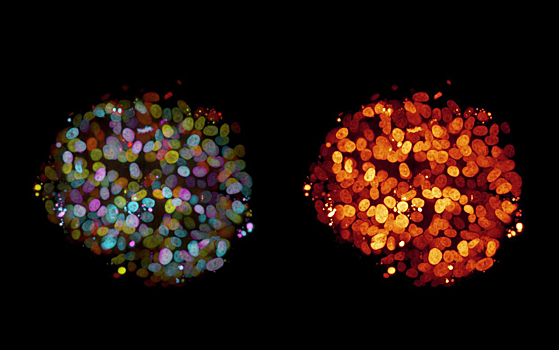

Исследователи из Санкт-Петербурга изучили эволюционный возраст генов человека и выявили существование их нового класса, проявляющего себя в опухолях. Это подтверждает сформулированную учеными ранее теорию эволюционной роли опухолей. Работа исследователей опубликована в журнале Scientific Reports. Опухоль — патологический процесс, представляющий собой новообразованную ткань, в которой из-за генетических изменений нарушена клеточная регуляция и, соответственно, функциональность. Опухоли подразделяют на доброкачественные и злокачественные. Доброкачественная растет медленно, не метастазирует, ее можно без проблем удалить. Злокачественное же новообразование, или рак, является одной из основных причин смерти в мире. Ученые обнаружили, что разные классы генов человека имеют различный эволюционный возраст. Эволюционно новые гены, особо активные в опухолевых клетках, могут использоваться в качестве маркера для рака. Это может послужить серьезным толчком для развития диагностики онкологических заболеваний. Ученые из Санкт-Петербургского политехнического университета Петра Великого и Санкт-Петербургского государственного университета обнаружили эволюционно новые гены человека, работающие во всех опухолях. Они получили название TSEEN-генов (Tumor Specifically Expressed Evolutionarily Novel). «Эволюционная роль этих генов состоит в том, что они являются генетическим материалом для возникновения новых прогрессивных признаков. TSEEN-гены проявляются во многих новообразованиях, поэтому могут стать лучшими опухолевыми маркерами», — рассказал один из исследователей, руководитель научно-исследовательской лаборатории «Молекулярная вирусология и онкология» СПбПУ Андрей Козлов. Согласно созданной ранее авторами теории, число онкогенов, стимулирующих образование опухоли, у человека соответствует числу дифференцированных типов клеток в организме. Также было сформулировано, что эволюция онкогенов, генов, подавляющих рост новообразований (генов-супрессоров), и генов, отвечающих за дифференцировку клеток, проходит параллельно. В основе данной теории лежит гипотеза об эволюции путем неофункционализации опухолей. Наследуемые новообразования могли играть важную роль в ранней эволюции многоклеточных организмов, предоставляя дополнительные клеточные массы для происхождения новых типов клеток, тканей и органов. Эти клеточные массы были важны и для экспрессии эволюционно новых генов, которые возникают в ДНК зародышевых клеток. Новые исследования коллектива лаборатории подтвердили упомянутую гипотезу на примере опухолей рыб. В них тоже работают эволюционно новые гены, гомологи которых есть и в геноме человека. Они участвуют в развитии прогрессивных признаков, которых нет у рыб (например, легких, молочных желез, плаценты, межжелудочковой перегородки в сердце и т. д.). Это подтвердило гипотезу об эволюционной роли опухолей. Исследования, о которых говорится в работе, проводились несколько лет. За это время был использован широкий перечень биоинформатических и молекулярно-биологических методов. «Разработанная теория предсказывает новые пути терапии и профилактики опухолей. Для решения проблемы рака необходимо создать новую модель терапии и диагностики в онкологии. Открытые TSEEN-гены могут быть использованы для создания новых онкологических тест-систем и противоопухолевых вакцин», — резюмировал Козлов. Понравился материал? Добавьте Indicator.Ru в «Мои источники» Яндекс.Новостей и читайте нас чаще. Пресс-релизы о научных исследованиях, информацию о последних вышедших научных статьях и анонсы конференций, а также данные о выигранных грантах и премиях присылайте на адрес science@indicator.ru.